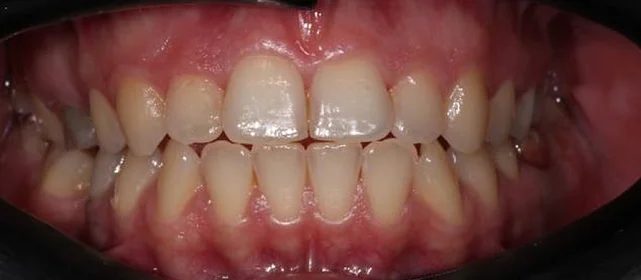

Скученность зубов, обе челюсти сужены — зубам не хватало места в ряду.

Брекет-система на обе челюсти. Расширить зубные дуги и убрать скученность. Срок — около 1,5 лет.

Проблема: Пациентка обратилась с одной жалобой — неровные зубы. При осмотре обнаружили, что обе челюсти сужены, зубам банально не хватает места, отсюда скученность. Зубы здоровые, ортопедия не нужна — чисто ортодонтический случай.

Решение: Установили брекеты на обе челюсти. Расширили дуги, убрали скученность — всё за 15 месяцев. Визиты раз в 4–6 недель для замены дуг. После снятия зафиксировали ретейнеры на обе челюсти, сняли сканы для кап. Ортопед подтвердил, что протезирование не требуется. Терапевт рекомендовал лечение — пациентка записана.